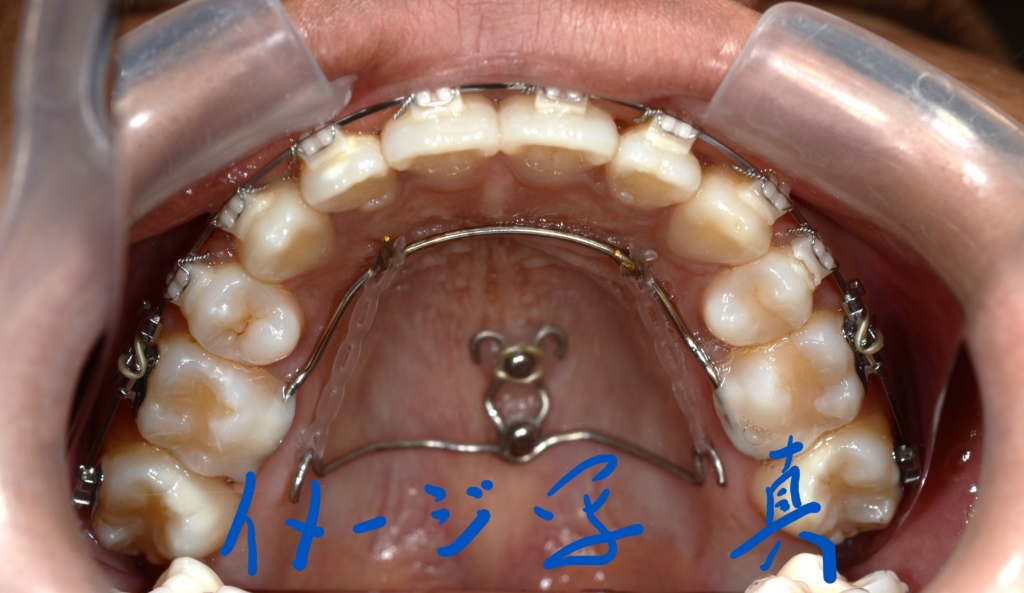

先ずは、その準備として上顎の口蓋にアンカースクリューを追加で植立します。

口蓋のアンカースクリューにPLAS&パラタルバーをセットして、上の歯列全体を後方へ移動させます。

同じ内容の治療をしている方のモノをイメージ写真として挙げています。